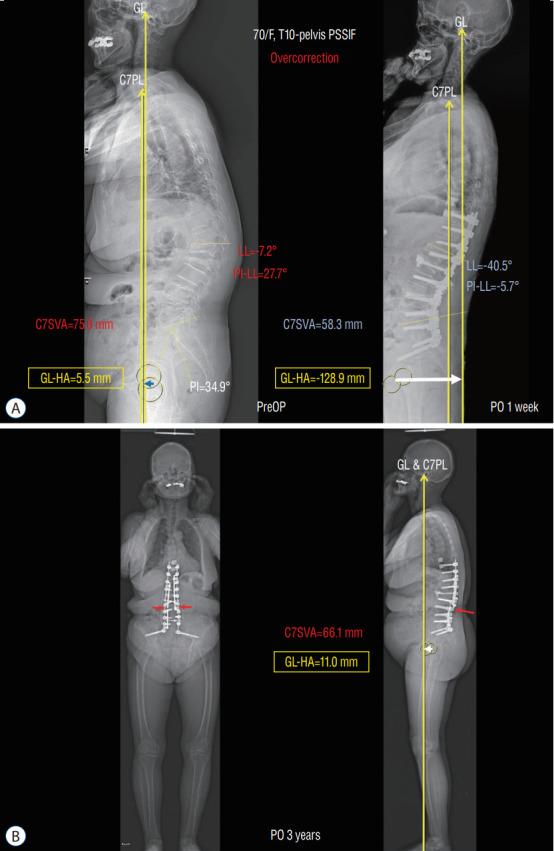

In adult spinal deformity (ASD) surgery, mechanical failure (MF) has been a significant concern for spine surgeons as well as patients. Despite earnest endeavors to prevent MF, the absence of a definitive consensus persists, owing to the intricate interplay of multifarious factors associated with this complication. Previous approaches centered around global spinal alignment have yielded limited success in entirely forestalling MF. These methodologies, albeit valuable, exhibited limitations by neglecting to encompass global balance and compensatory mechanisms within their purview. In response to this concern, an in-depth comprehension of global balance and compensatory mechanisms emerges as imperative. In this discourse, the center of gravity and the gravity line are gaining attention in recent investigations pertaining to global balance. This narrative review aims to provide an overview of the global balance and a comprehensive understanding of related concepts and knowledge. Moreover, it delves into the clinical ramifications of the contemporary optimal correction paradigm to furnish an encompassing understanding of global balance and the current optimal correction strategies within the context of ASD surgery. By doing so, it endeavors to furnish spine surgeons with a guiding compass, enriching their decision-making process as they navigate the intricate terrain of ASD surgical interventions.